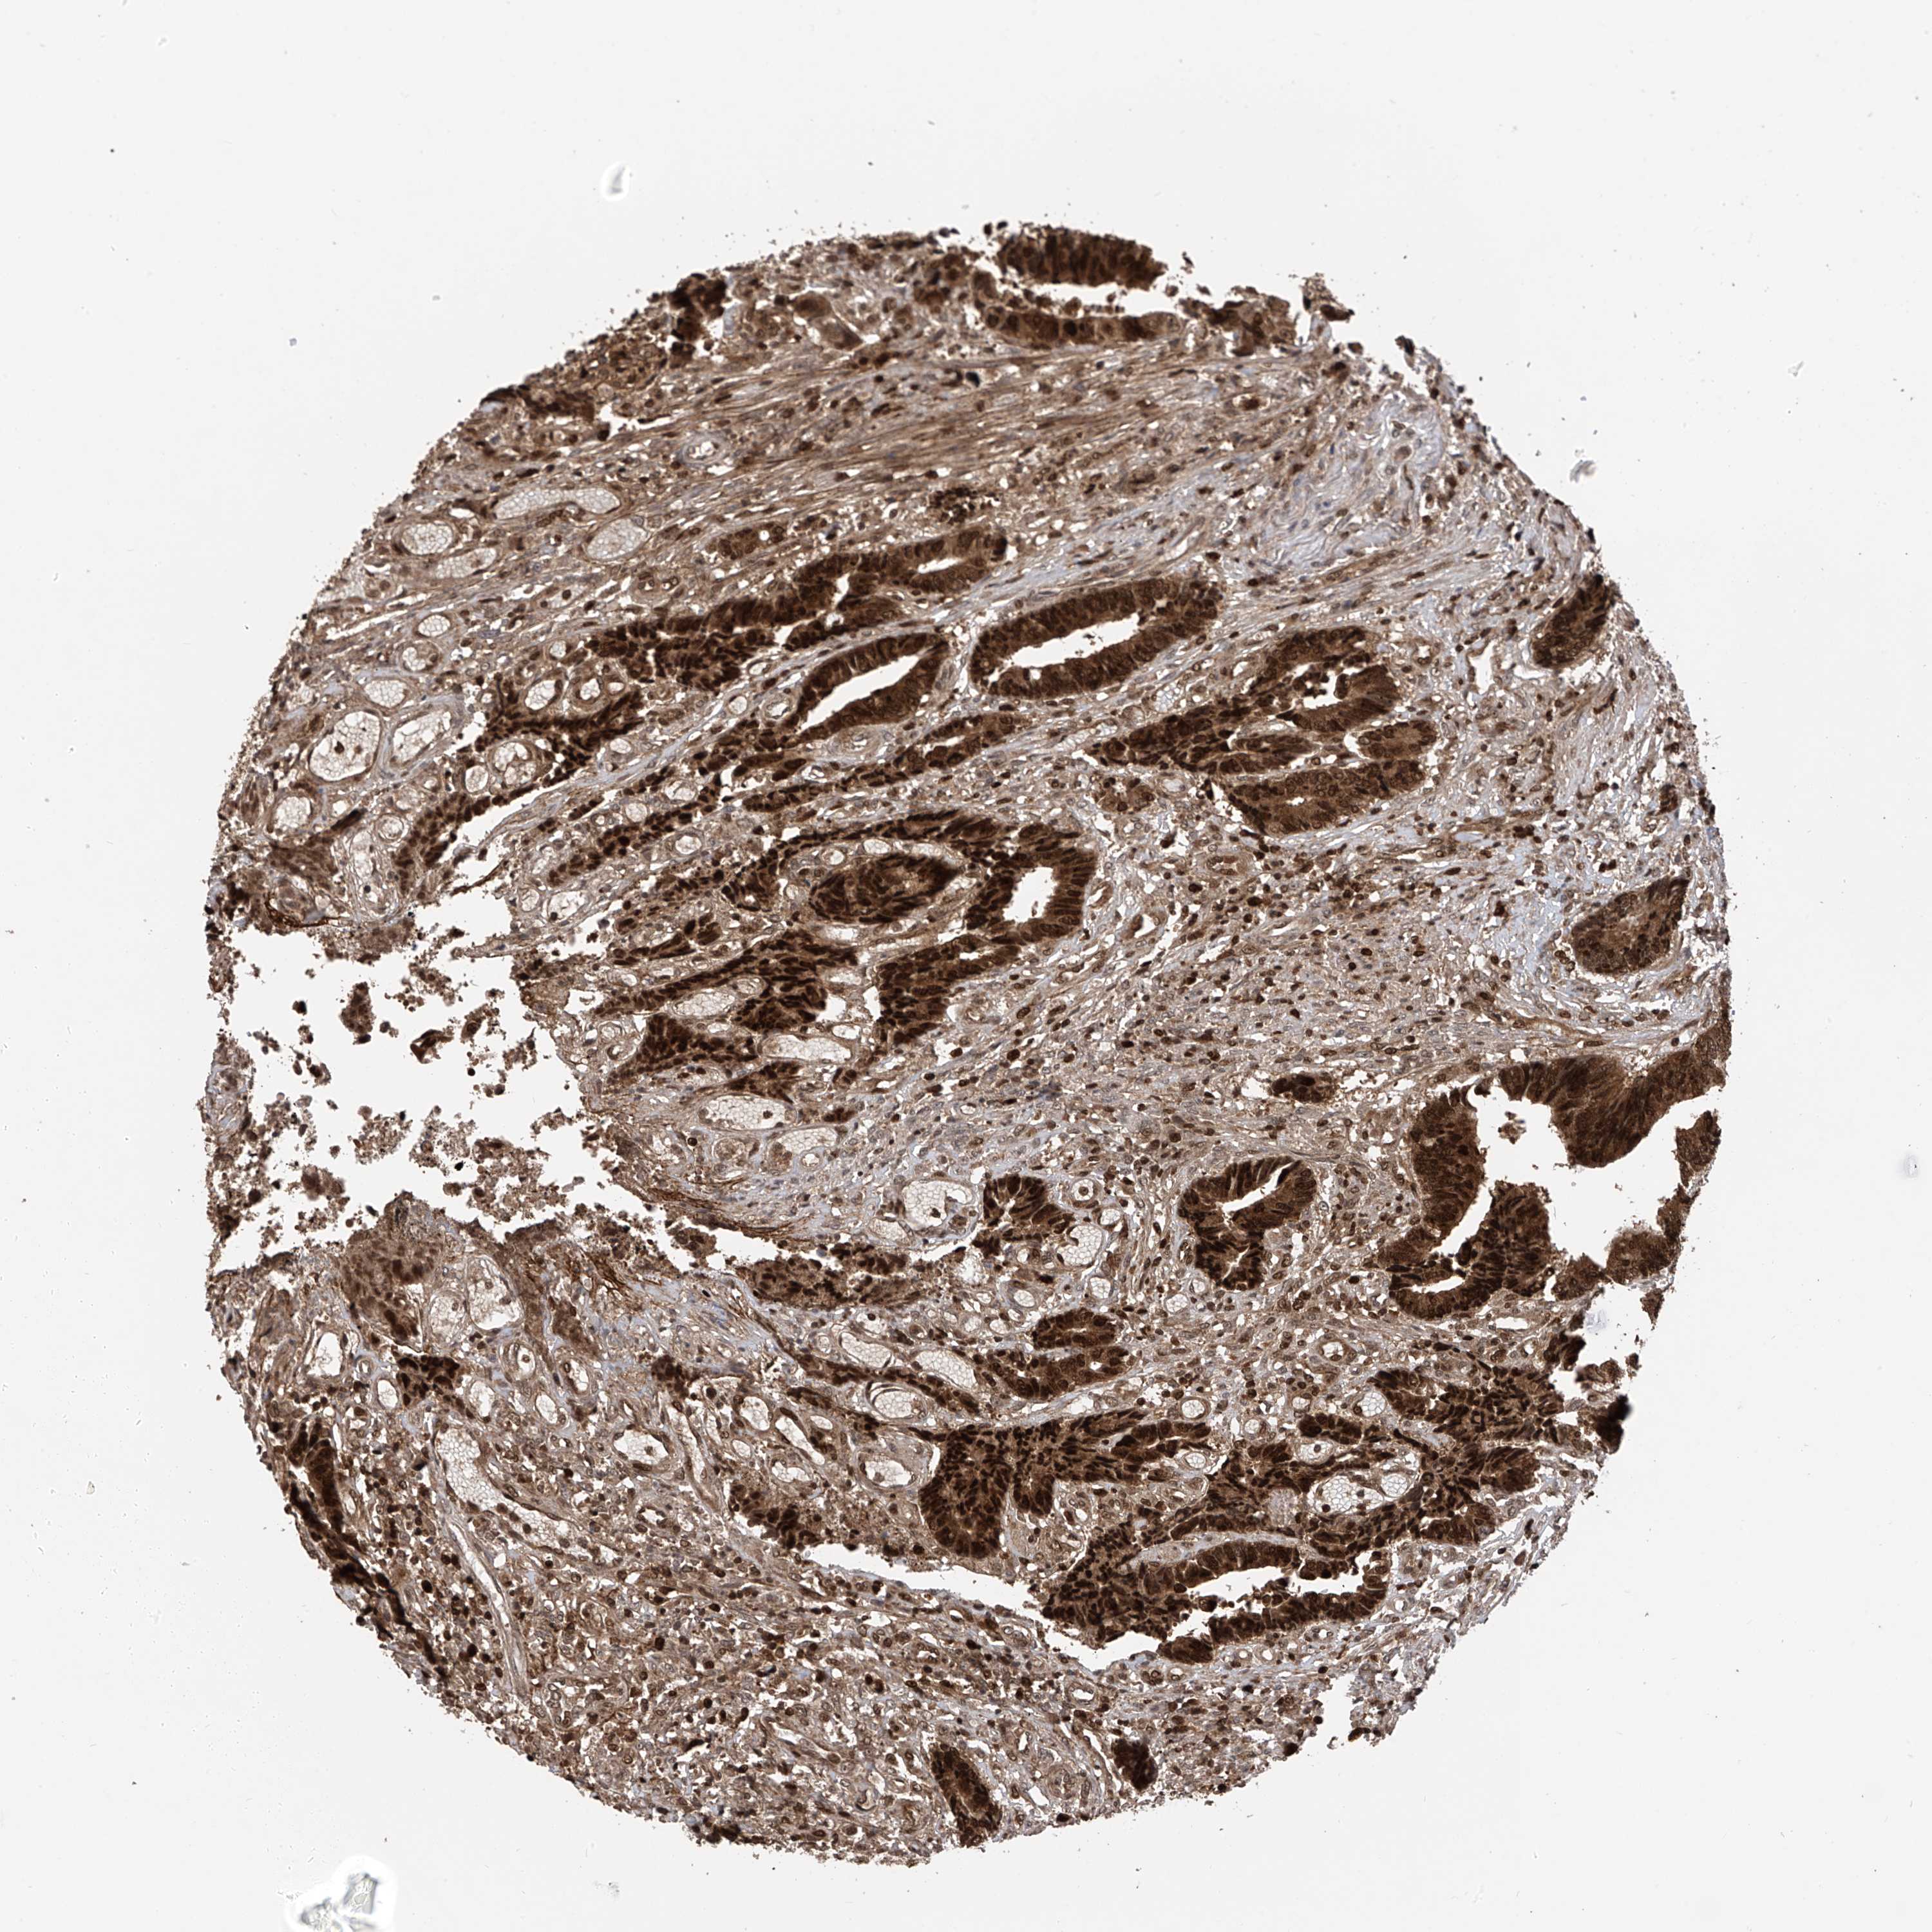

CANCER COLORECTAL CANCER Show tissue menu

Colorectal cancer

Colon adenocarcinoma